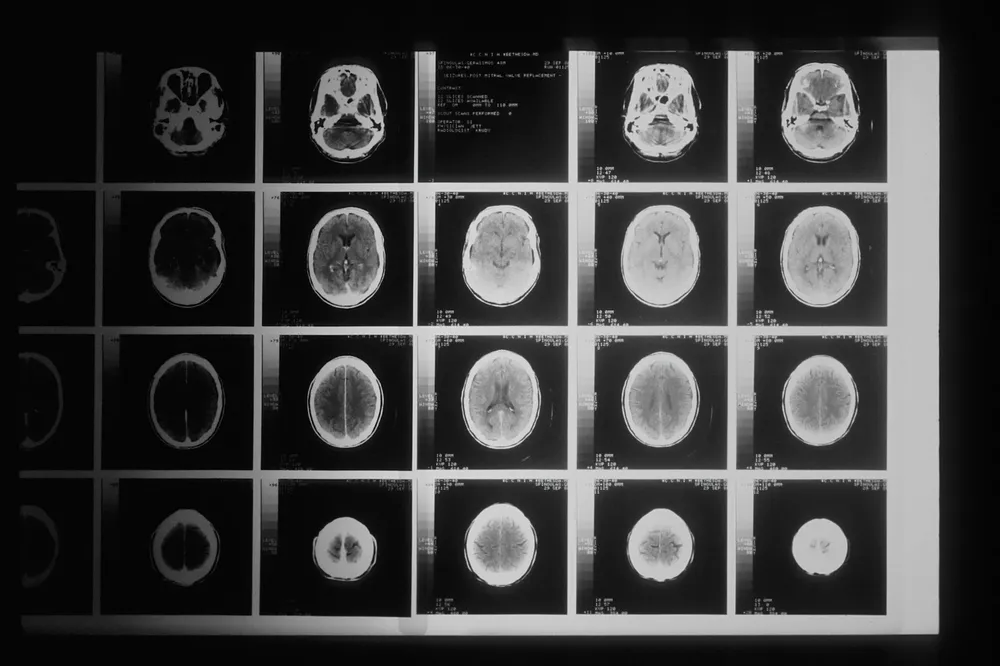

En MR-scanning af kraniet kan foretages med henblik på at lokalisere en evt. tumor. Øjenundersøgelser laves med henblik på, om der er påvirkning af synsnerven.